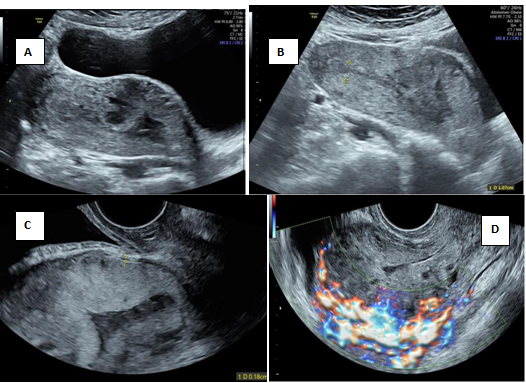

An abortion in progress or the inevitable abortion is the condition where the products of conception have detached from the implantation site and continuation of pregnancy is not possible. The ballooning of the cervical canal due to retention of the abortus by the resistant external os in spontaneous abortion can rise the suspicion of cervical pregnancy.1 A non-viable sac passing through the cervix will have no peritrophoblastic flow and this serves as an initial clue. Figure 1 is an illustration of cervical stage of miscarriage, showing an open external os with products of conception in the cervical canal with absent peritrophoblastic flow. Short-term follow-up of a failed pregnancy will demonstrate lack of interval growth, and confirm that the gestational sac is not fixed in location and will have a positive sliding sign.2 Both cervical ectopic pregnancy and CSP often contain live embryos with detectable cardiac activity, while an abortion in progress will not. A combination of gray scale and colour doppler findings helps to differentiate the two entities.3,4

Figure 1 Cervical stage of miscarriage.

A) Transabdominal ultrasound showing echogenic mass seen in the cervical canal with splaying of anterior and posterior lip of cervix[*] B) Demonstration of open external os with products of conception in cervical canal C) Transverse section of cervix showing distended cervix with echogenic mass D) No evidence of peritrophoblastic vascularity seen surrounding mass.